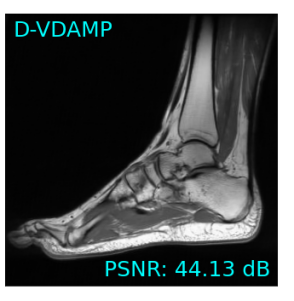

Single-coil results: Table 1 shows that D-GEC outperformed D-VDAMP in all single-coil experiments and outperformed PnP-PDS in all but SSIM at . Figure 5 shows an example of the wavelet coefficients input to D-GEC’s denoiser at the 10th iteration, and their error relative to the true coefficients. Figure 3 shows the evolution of the standard deviation at the input to D-GEC’s denoiser in each subband; there is a good agreement between true and predicted values. Figure 6 suggests that the subband errors are Gaussian. Figure 4 shows image recoveries and error maps for one test image at .